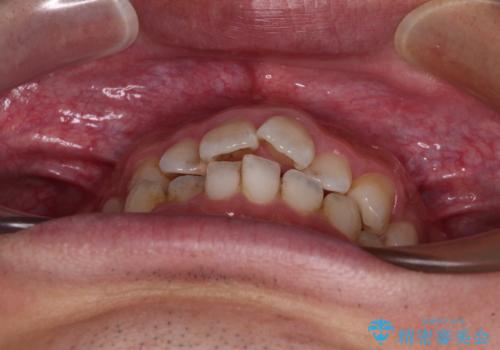

前歯のデコボコと突出感をマウスピース矯正できれいに

- 上下前歯のデコボコと突出感を気にして来院された患者様です。

目立たない装置を希望されたため、インビザラインによるマウスピース矯正を行うこととしました。